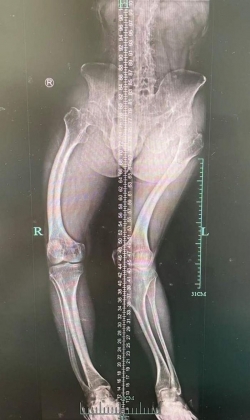

Phim chụp xương sống của anh Lý Vũ Dũng.

Bác sĩ Hoàng Giải - Phó trưởng khoa Khoa Thấp khớp và Miễn dịch đã tiếp nhận trường hợp của anh Lý. Sau khi chụp X-quang và kiểm tra sinh hóa, bác sĩ phát hiện, anh Lý không chỉ bị biến dạng xương nghiêm trọng mà còn bị hạ canxi máu.

Tuy nhiên, khi lớn hơn, tình trạng của Lý trở nên tồi tệ, anh mắc chứng chứng vẹo cột sống và chứng vẹo đầu gối (chân chữ X) điển hình, chiều cao không phát triển, khi trưởng thành cố định ở mức 1m48.